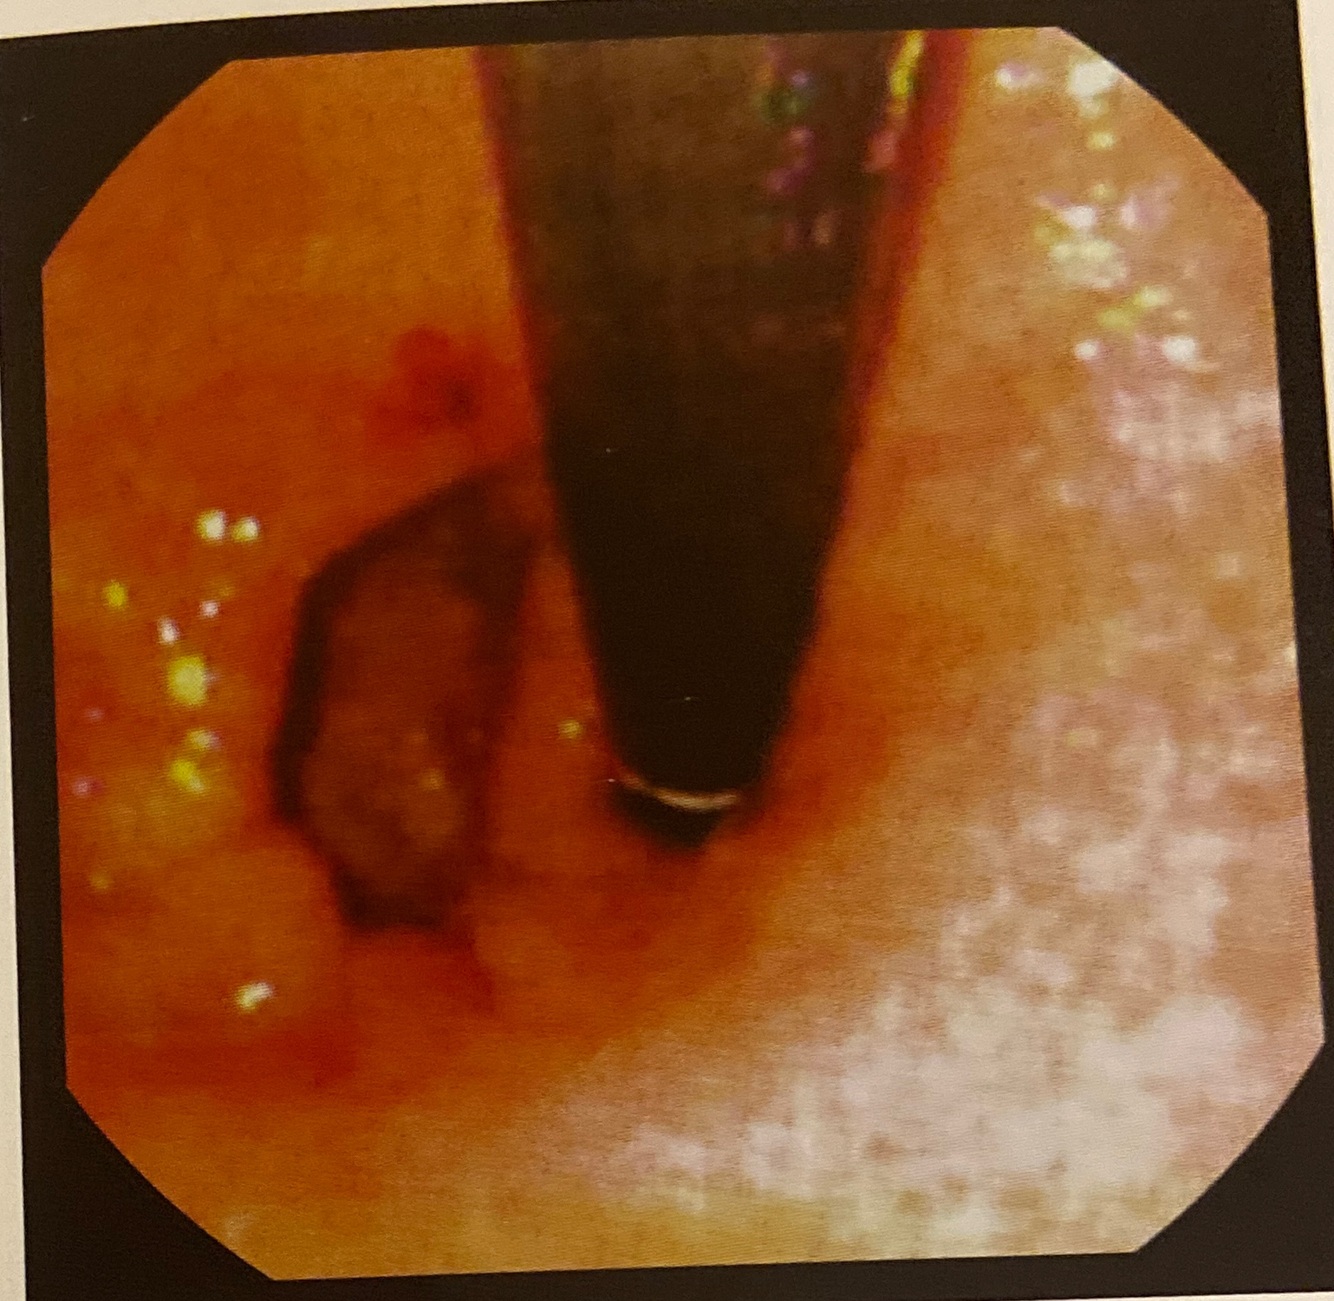

Esôfago

Câncer esofágico